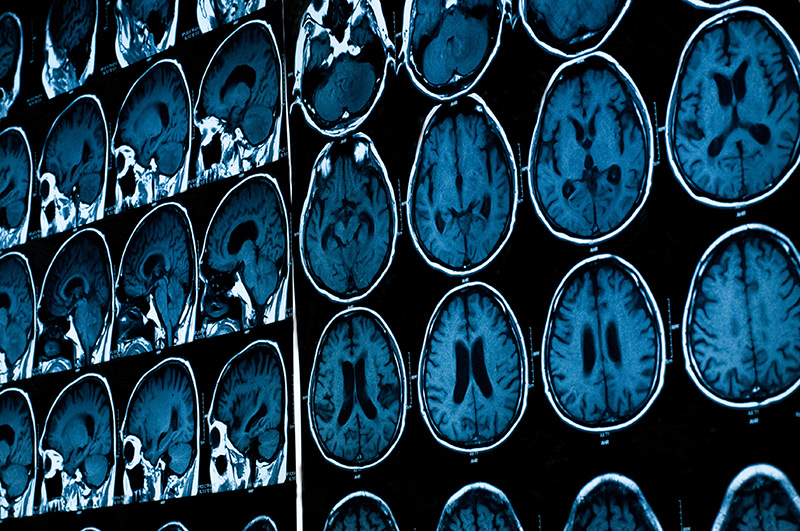

Neuroimaging enjoys an increasing prominence, not only among medical doctors, neuroscientists and philosophers, but in society at large. Brain images are deeply compelling, and are claimed to provide windows into the living brain. Yet what these images really show remains a debated issue. The research project Picturing the Brain: Perspectives on Neuroimaging seeks to deepen our understanding of the epistemological roles neuroimaging technologies play in the conduct and communication of medicine and science. The primary objective is, more precisely, to develop a fine-grained understanding of socio-cultural and ethical issues that arise in relation to current applications of these technologies, as they are put to use as cognitive tools, as perceptual prostheses, and as visual rhetoric. To pursue this goal, we will carry out interactionist in-depth studies of the design and use of two key applications of neuroimaging, brain mapping and neuronavigation, proceeding from these to questions concerning computational brain modelling and simulation in science. The project will also investigate prospects and issues relating to the persuasive force of neuroimaging against the background of the current overwhelming demand for brain images. This includes exploring issues relating to neuroenhancement and to the ways that neuroimaging reframes the brain-mind relationship, fostering deep changes in how humans perceive themselves. The project is interdisciplinary and allows researchers with backgrounds in media studies, philosophy, digital media engineering, medical imaging, neuroscience, and creative arts to work together on specific tasks in varying configurations. The research is divided into three work packages focusing, respectively, on cognitive, prosthetic, and rhetorical functions of neuroimaging. A fourth package takes the form of a project laboratory for experimenting with different modes of integrating science, technology and society through artistic interventions.

Advanced imaging technologies are currently transforming operating rooms into sophisticated augmented reality studios that explore recent developments in computer visualization, navigation applications, and robotic systems. The new imaging methods promise to increase precision and improve health outcomes. However, as medical diagnosis and therapy grow more dependent on images, the status and roles of these images become increasingly controversial. Image-guided applications reshape clinical practices, impact medical decisions, and transform the relationship between physician and patient. The objective of the project is to develop a new framework that accounts for the active role of images in surgical contexts, providing a systematic basis for handling the impact of these images and assessing their controversial aspects. The project pursues its goal through a collaborative and interdisciplinary effort that involves medical practitioners. It articulates the visual knowledge of medical practitioners by undertaking in-depth operational analyses of three image-guided technologies in current use: the 3D Slicer software application, the da Vinci surgical system, and the CyberKnife robotic radiosurgery system. The analyses introduce the notion of styles

of objectivity, which accounts for the key features of these applications, including agency, alignment, and automation, while acknowledging that images have a certain agency and that there is an inner connection between aesthetic and epistemic factors. A second objective of the project is to contribute to conceptual and methodological innovation through a two-way transfer of visual literacies across medicine and humanities/social science domains, by operationalising the visual knowledge of medical practitioners so that it can be fed into visual/media/science studies, and vice versa. This includes developing concepts for new ways of teaching the visual knowledge of medicine.